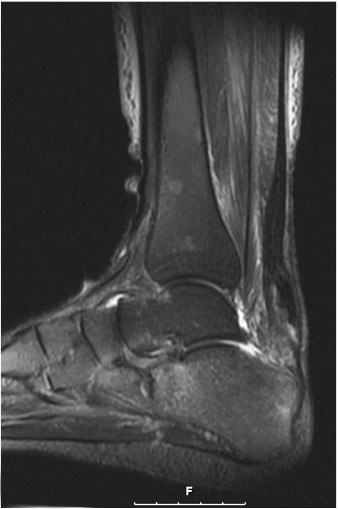

Der geübte Untersucher kann anhand des seitlichen Röntgenbildes die Diagnose einer Achillessehnenruptur stellen. Die Konturen des Kager-Dreiecks – gebildet von der ventralen Begrenzung der Achillessehne, der posterioren Tibiakante und der kranialen Kalkaneuskortikalis – verstreichen im Rupturfall (Kager 1939). Die MRT- Diagnostik spielt für die Primärdiagnostik der frischen Achillessehnenruptur eine untergeordnete Rolle und ist im Normalfall nicht notwendig. Anders verhält es sich bei den chronischen Rupturen. Hier ist die MRT ein wichtiges Diagnostikum insbesondere in Hinblick auf die Beurteilung der Sehnen- und Muskeldegeneration (Abb. 6).

Abbildung 6

Neben der strukturellen Wiederherstellung der Sehne ist die funktionelle Beurteilung des Muskels von entscheidender Bedeutung. Ist es bereits zu einer Degeneration der Muskeln gekommen, kann ein gutes funktionelles Ergebnis, trotz subtiler Sehnenrekonstruktion, nicht erreicht werden. Die Arbeitsgruppe um Hoffmann et al. 13 konnte in ihrer Arbeit zeigen, das es - ähnlich wie bei Patienten mit chronischen Supraspinatusrupturen - zu fettigen Degenerationen und Ödemen der Muskulatur kommt, die im MRT nachweisbar sind. Wir empfehlen die MRT- Untersuchung des gesamten Unterschenkels und nicht nur die rupturnahen Bereiche. Des Weiteren lässt die MRT eine Beurteilung der Degeneration der umliegenden Sehnenanteile zu. Die Computertomographie sollte nur in Ausnahmefällen zum Ausschluss von Begleitverletzungen (Abb. 7) durchgeführt werden und gibt uns sonst keinen weiteren Informationsgewinn.